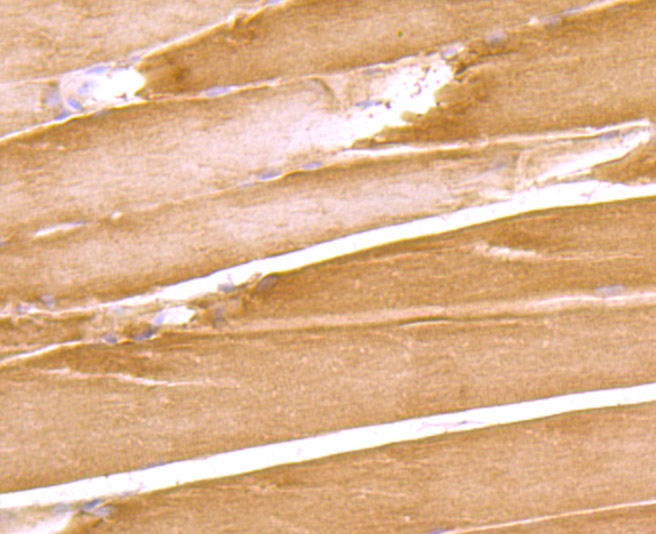

Immunohistochemical analysis of paraffin-embedded rat skeletal muscle tissue using anti-DOCK4 antibody. Counter stained with hematoxylin.